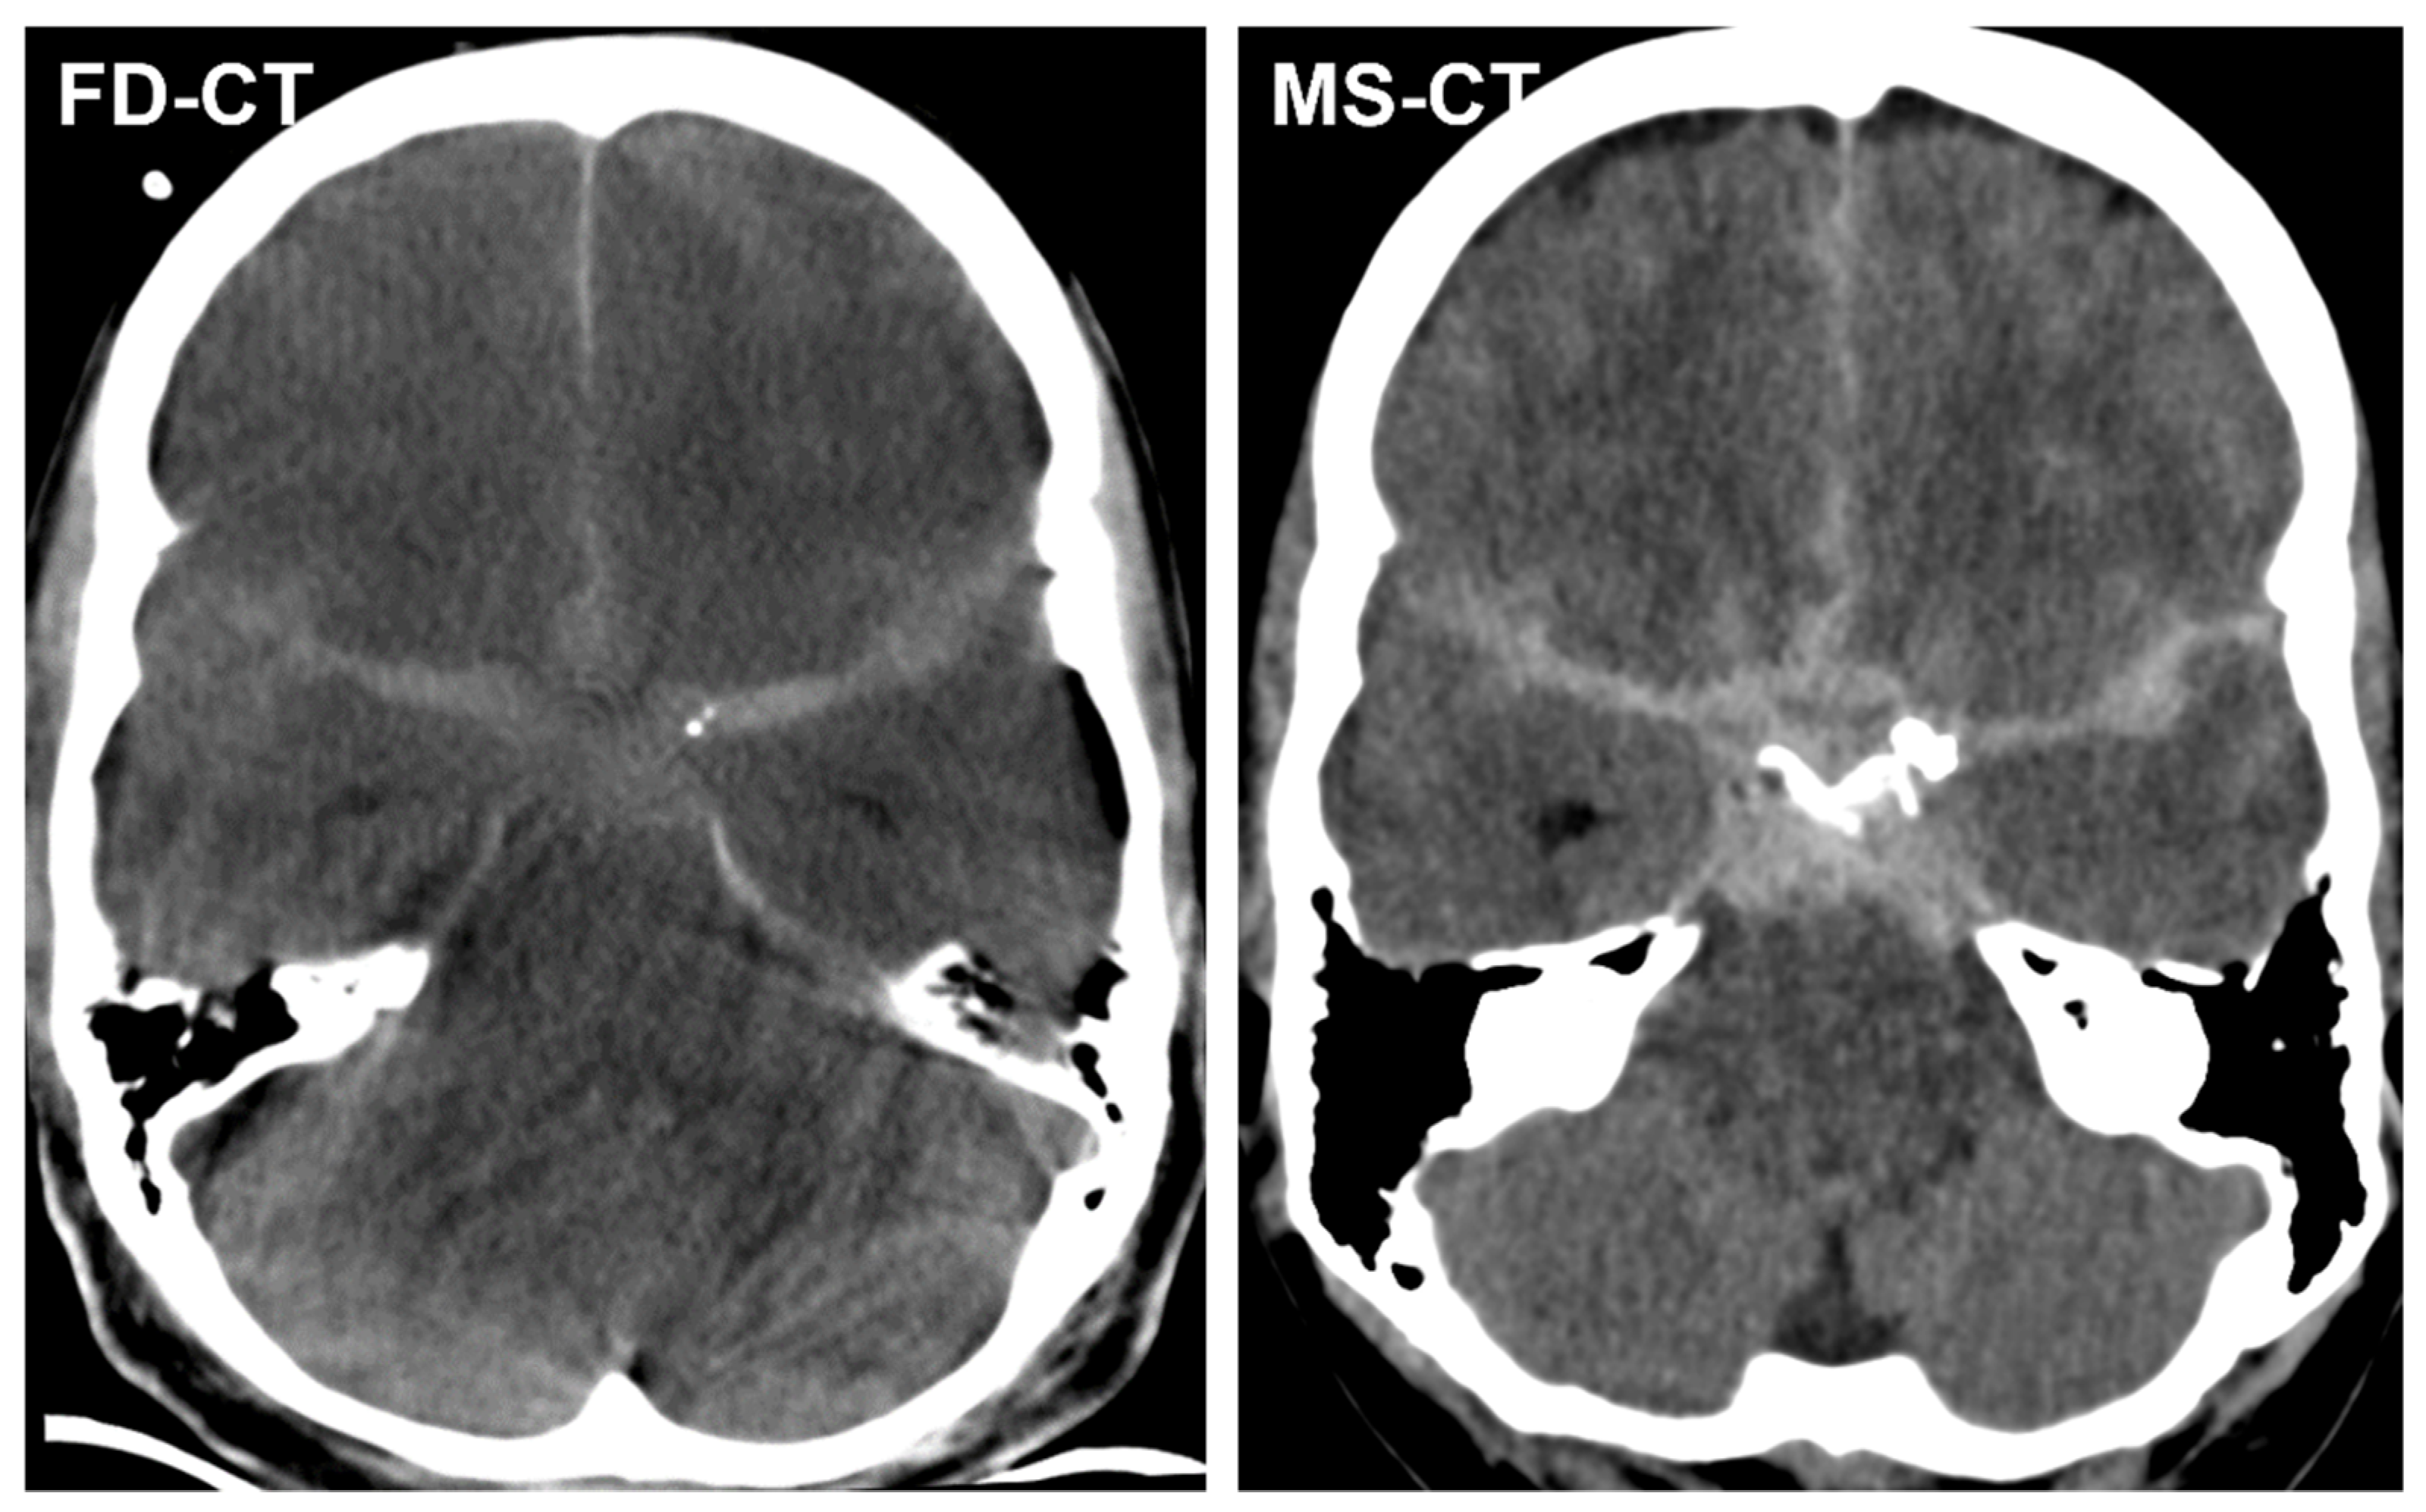

3.3.1. Blood Distribution

3.3.2. External Ventricular Drain Position

3.3.3. Acute Obstructive Hydrocephalus

3.4. Quantitative Analysis

3.4.1. Cella Media Distance